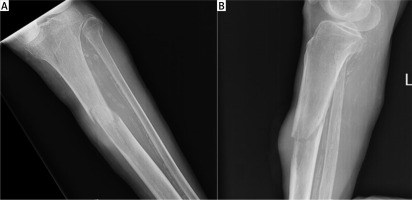

On the 17th postoperative day, during a regular walk, the patient fell and broke a leg. She was brought to our emergency department, where a pathologic fracture of the proximal tibial diaphysis was diagnosed on X-ray, just at the level of the prior incision (Figures 2 A, B). Laboratory analysis showed signs of anaemia with a slightly decreased haemoglobin level (108 g/l; NL 119–157 g/l) and decreased erythrocytes (3.81 × 106/ml; NL 3.86–5.08 × 106/ml). The CA-125 tumour marker was elevated (36.3 kIU/l; NL < 35 kIU/l), and AFP was also slightly increased (11.5 µg/l; NL < 9 µg/l).

The patient underwent emergency surgery, and osteosynthesis was achieved by means of external bone fixation (Figure 3). Intraoperatively, a biopsy of the altered bone tissue from the fracture site was taken. The pathological examination revealed metastatic colorectal adenocarcinoma. During the hospitalization, a broad diagnostic work-up was undertaken. MSCT of the abdomen, thorax, and lower extremities was obtained and revealed rectal tumour with no signs of metastases apart from the osteolytic lesion in the fractured left tibia (Figures 4 A–C). Furthermore, a colonoscopy was done, and a circular mass in the upper rectum, about 12 cm from the anal verge, was found (Figure 5). Pathological examination of the tumour specimen obtained at colonoscopy confirmed a moderately differentiated primary adenocarcinoma of the rectum. The patient was presented at a multidisciplinary tumour-board, where it was decided to perform a resection of the primary tumour and a femoral amputation prior to chemotherapy.